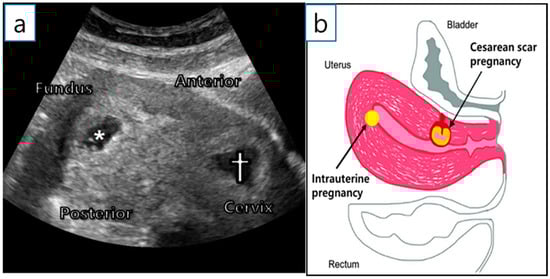

A 36-year-old woman (gravida 2, para 1) was transferred from a local hospital because of a cesarean ectopic pregnancy with IUP. The patient underwent in vitro fertilization-embryo transfer (IVF-ET) using two ova. Two years ago, she delivered a baby via a lower segment cesarean section. Ultrasonography at 6+1 gestational weeks (GW) revealed two gestational sacs; one in the uterine fundus and the other in the anterior uterine isthmus (Figure 1a,b). Both had fetal cardiac activity, and the mother had no vaginal bleeding or abdominal pain.

Figure 1. Initial examination. (a) Initial transvaginal ultrasound examination at 6+1 GW. *—intrauterine gestational sac; †—CSP. (b) Description of sagittal plane.